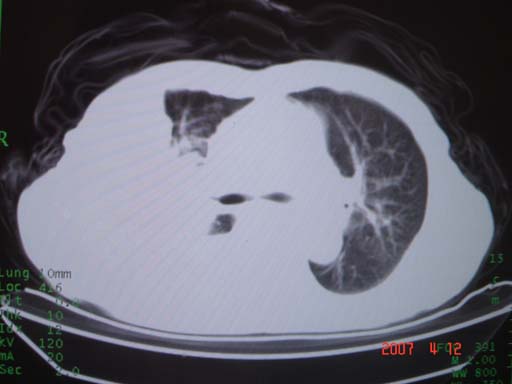

帮我 看看。男77岁咳嗽咯血2月发热2周!病人一般情况可 口痰为鲜红,有点象洗肉水(我看见他吐的痰了)

为何只有这么几幅图像?连纵隔窗都没有。但我发现上叶支气管显示不清,再加上年纪大,咯血等症状,恶性肿瘤首先得考虑。

考虑右肺新生物伴右中上肺阻塞性肺炎及含气不良,右侧胸腔积液。建议痰与纤支镜检查

考虑右侧中央型肺癌伴中上肺阻塞性肺炎、不张,胸腔积液。,建议支纤镜检查。

考虑:右上肺癌伴中上叶炎症,右侧胸腔积液。

图片不太全

根据患者老年男性,右肺上叶支气管狭窄、阻塞,伴阻塞性肺炎,考虑中心型肺癌可能性大。建议支气管镜检查

病灶局限在右肺中上叶,呈大片状实变影,内见空气支气管征,支气管分支较柔软,纵隔内未见肿大淋巴结.支持:感染性病变_1 大叶性肺炎.2 干酪性肺炎.

优先考虑右上肺干酪性肺炎并同侧中叶播散、胸腔积液。分析:右膈肌未见升高、纵隔未见明显右移,胸部各组淋巴结未见可疑肿大,中叶可见支气管铸形,肺野、肺门未见可确定肿块。

右肺上叶后段支气管中断,首先考虑中央型肺癌并右肺不张及纵隔淋巴结转移,右侧胸腔积液。

右肺上叶实变,实变范围如此之大,如果用肺癌解释的化,应该是比较大的支气管开口发生完全阻塞,但观察上叶前后段支气管还是比较通畅,所以应考虑感染性病变,大叶性肺炎可能,建议抗炎治疗后复查。